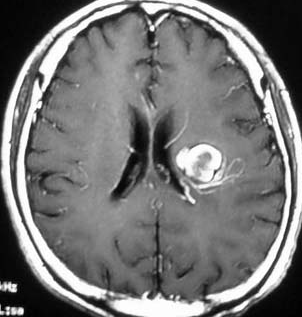

左は脳出血のCTです。海綿状血管腫からの出血を疑ったので造影のMRI(右の写真)をしました。血腫の周りに細い線がたくさん見えます。これが静脈奇形(静脈性血管腫)です。脳血管撮影DSAをしなくてもこの合併はわかるのです。この静脈奇形を手術で傷つけるとかなり広い範囲で脳梗塞がおきる可能性があります。